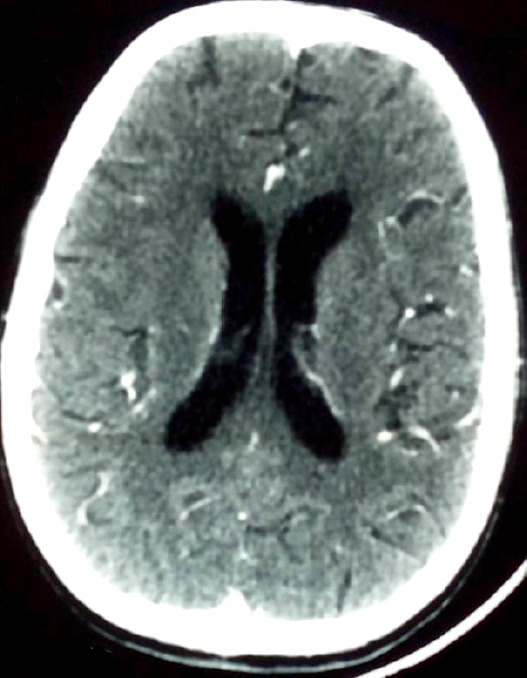

Case description: The patient presented with fever (39.3°C), general deterioration, Glasgow Coma Scale score of 10/15 without motor deficits, neck stiffness, and helmet-like headache unresponsive to analgesics. The patient had a CD4 count of 932 cells/mm3. No other immunosuppressive conditions were noted. The diagnosis of NMC was confirmed based on clinical and microbiologic findings. The patient was successfully treated in Bamako using an alternative protocol with fluconazole, a more accessible, less expensive treatment with fewer side effects compared to amphotericin B.

Abstract Image